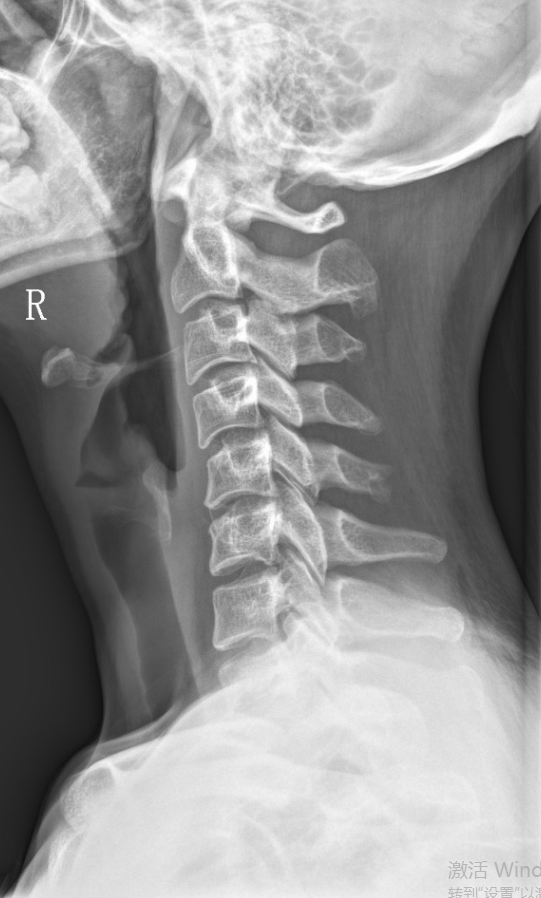

【影像】广州中医药大学深圳医院MR示:C5-6间盘膨出,L4-5间盘突出。X线示颈椎反弓伴侧弯,寰齿侧间隙右宽左窄,寰椎左侧侧块小。

【诊断】颈椎病;寰枢椎半脱位;